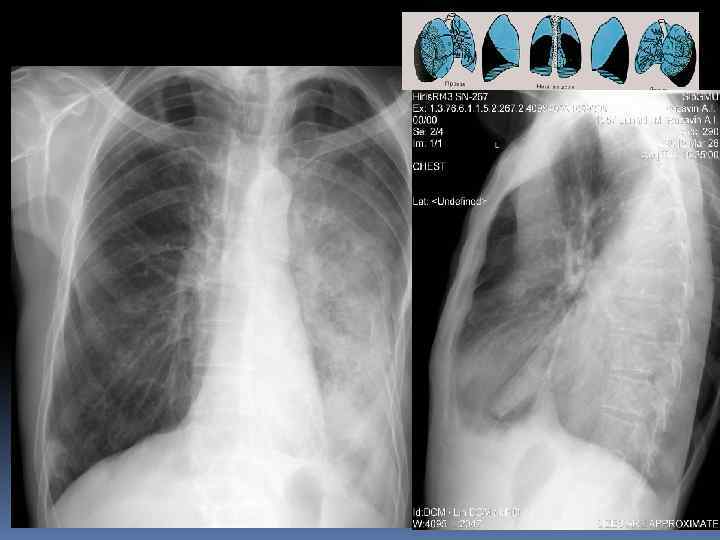

Легкие. Проекция долей легких. Правое легкое: две междолевые щели делят легкое на три доли. Левое легкое имеет две доли Пространственное расположение междолевых щелей. Топография долей легкого.

Междолевые борозды. Борозда между нижней и верхней, средней долями справа и верхней и нижней долями слева - главная междолевая борозда, имеется с обеих сторон. Справа между верхней и средней долями расположена дополнительная, малая горизонтальная междолевая борозда. Борозды бывают неполными, могут встречаться дополнительные борозды, образующие доли. Борозда состоит из двух слоев плевры, между которыми имеется потенциальная щель. В месте перехода грудной стенки в диафрагму, слои плевры образуют острый угол – синус (заворот): реберно диафрагмальный, реберно – медиастинальный. Задние реберно-диафрагмальные синусы самые глубокие, вытянуты в каудальном направлении.

Междолевые борозды.